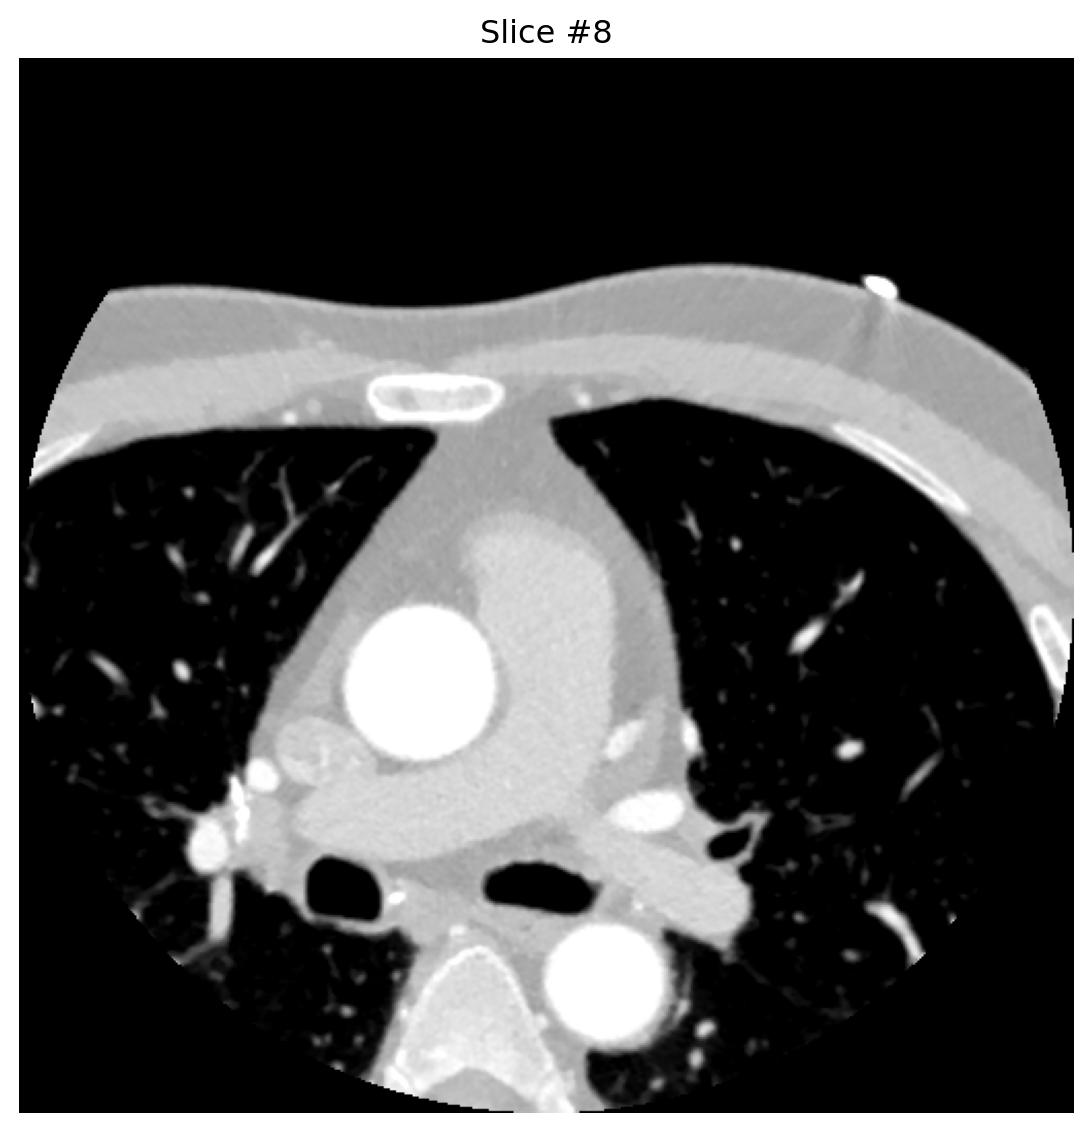

2.2. Processing + Visualization

def analyze_dicom_slice(slice_index):

buffer = BytesIO(dcb_stream.get_dicom_for_frame(slice_index))

dataset = pydicom.dcmread(buffer, force=True)

pixels = dataset.pixel_array.astype('float32')

if hasattr(dataset, 'RescaleIntercept'):

pixels += float(dataset.RescaleIntercept)

plt.figure(figsize=(8, 6))

plt.imshow(pixels, cmap='gray', vmin=-800, vmax=300)

plt.axis('off')

plt.title(f"Slice #{slice_index}")

plt.tight_layout()

plt.show()

return dataset

for idx in [0, 4, 8]:

analyze_dicom_slice(idx)

Conversion happens only when requested—no need to pre-expand entire series, saving space and latency.